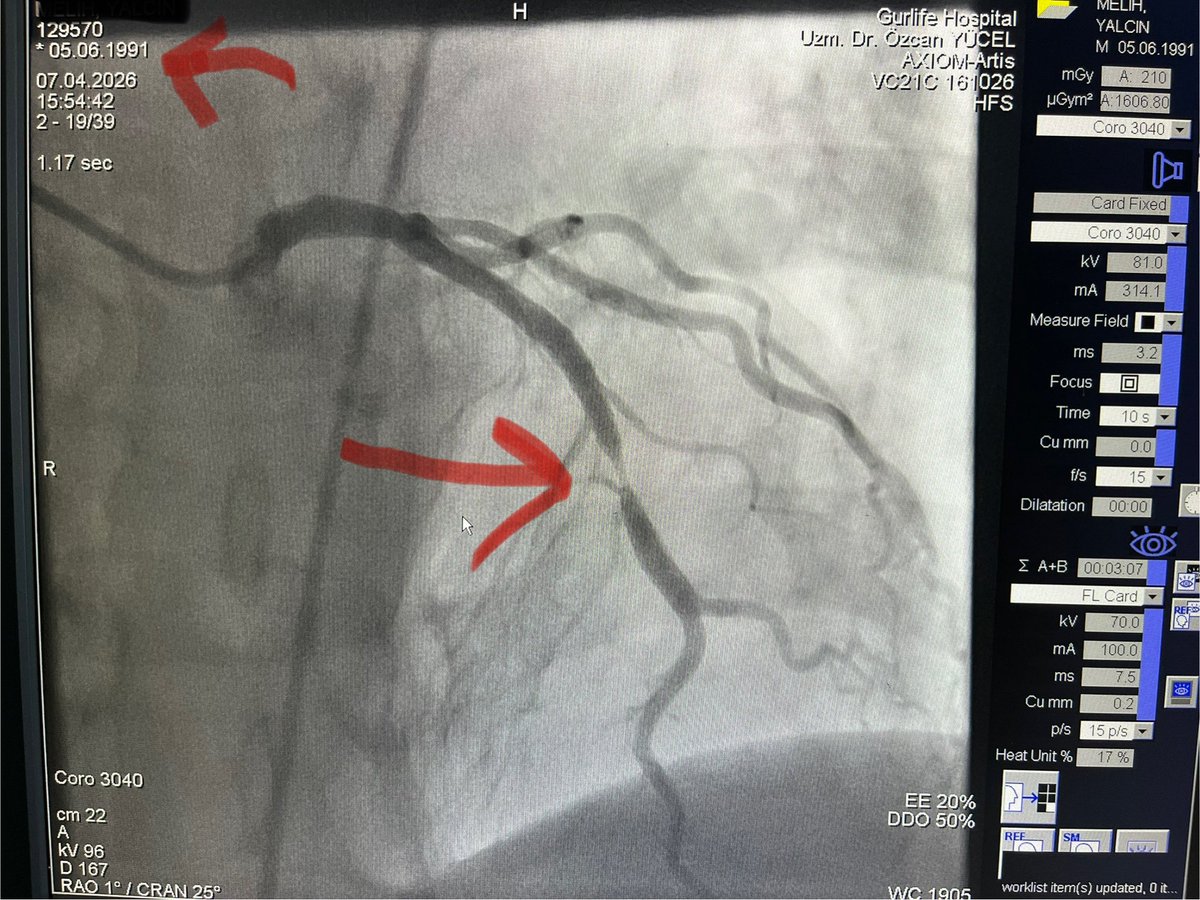

Dr. Özcan Yücel MD

Dr. Özcan Yücel MD@drozcanyucel·

Genç kalp krizleri gelmeye devam ediyor. Eskiden 30’lu yaşlarda kalp krizi 1 ya da 2 yılda bir gelirdi. Şimdi nerdeyse ayda 1 geliyor. (Üstteki kırmızı ok hastamın doğum tarihini, alttaki kırmızı ok tıkalı damar segmentini gösteriyor)